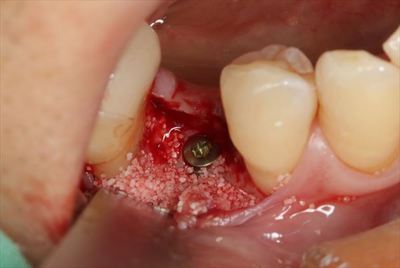

封鎖スクリューでインプラントフィクスチャーのスクリューホールを封鎖します。

![]()

封鎖しました。

骨吸収を防ぐため、デコルチケーション後にハイドロキシアパタイトを填入します。